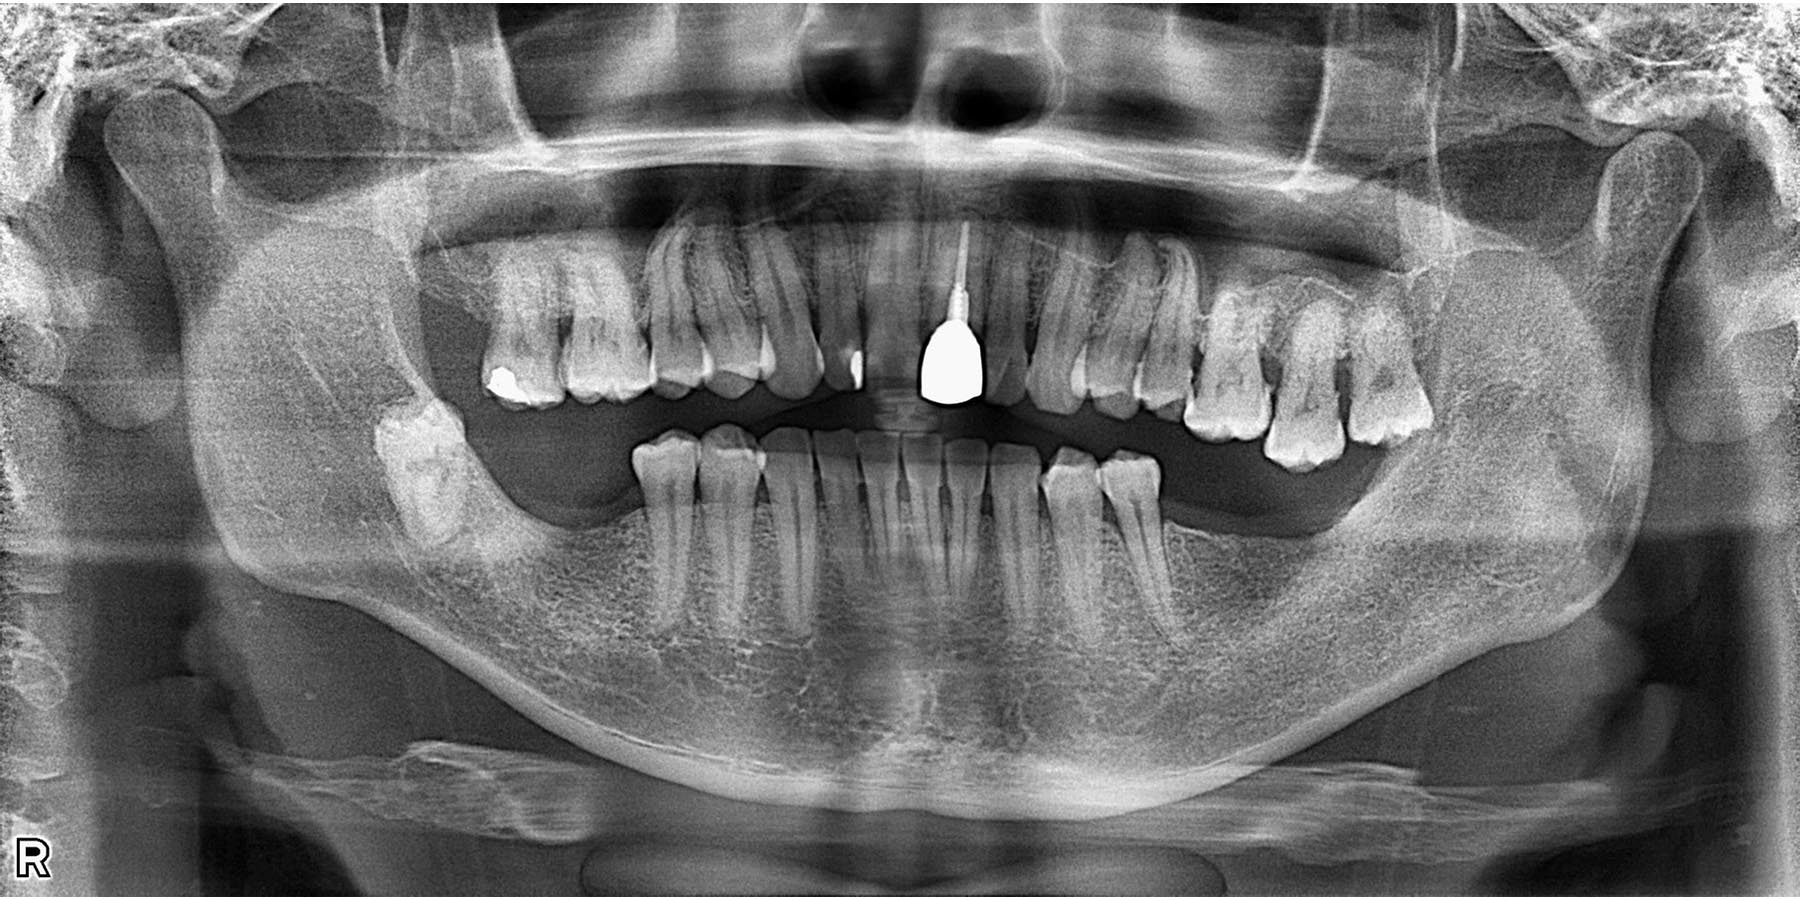

治療前